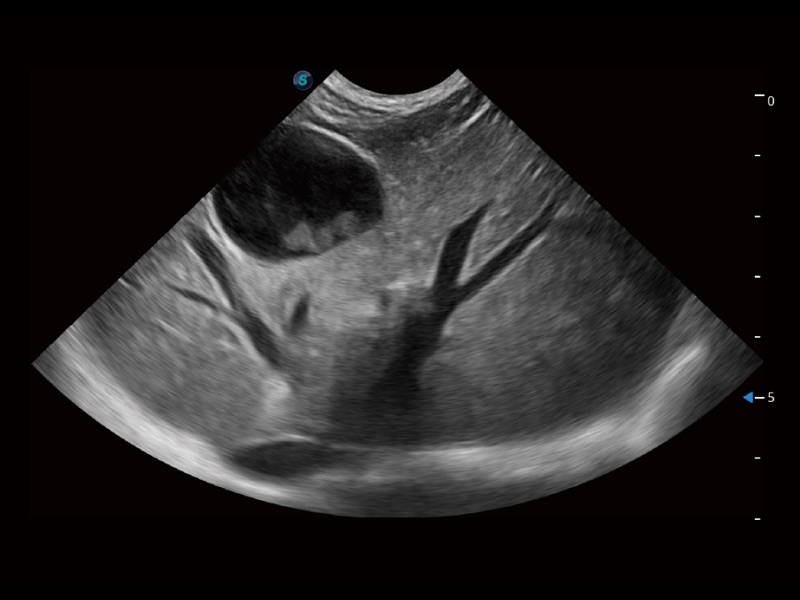

(犬)四腔心

(犬)四腔心MQA